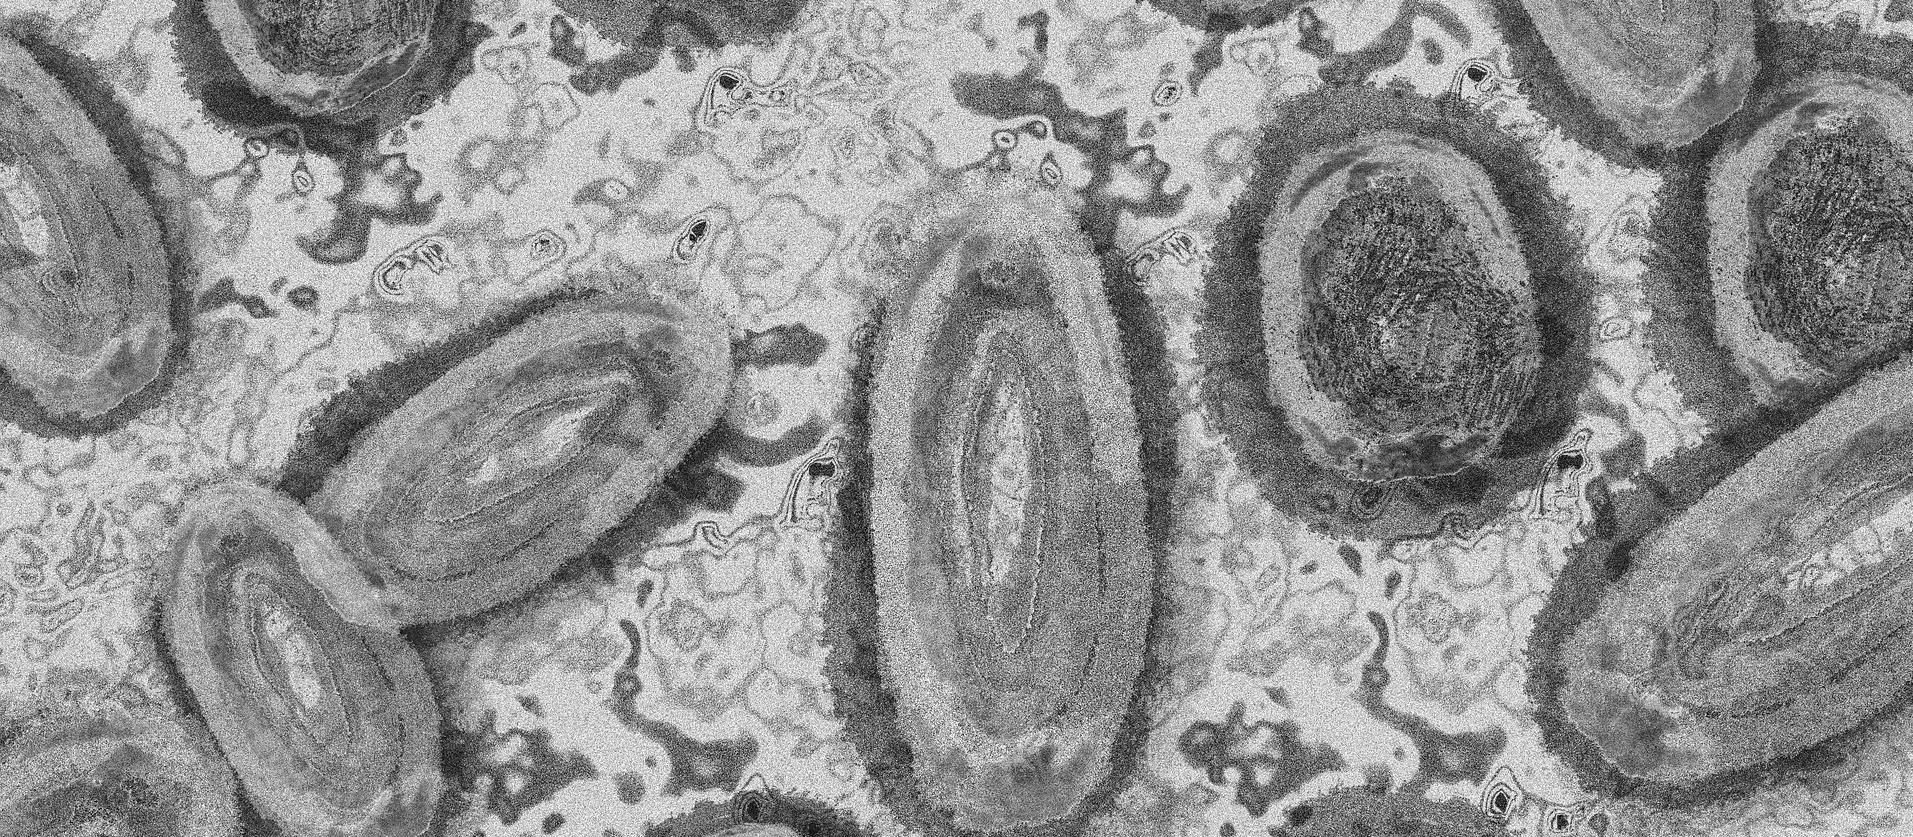

Imagem Ilustrativa/Representação abstrata do vírus da varíola/Gerd Altmann/Pixabay

Através do boletim divulgado nessa terça-feira (27) pela Secretaria de Estado da Saúde (SESA-PR), foi confirmado o primeiro caso de varíola dos macacos na cidade de Ponta Grossa. Além desse, foram confirmados mais 37 novos casos da doença em todo o Paraná.